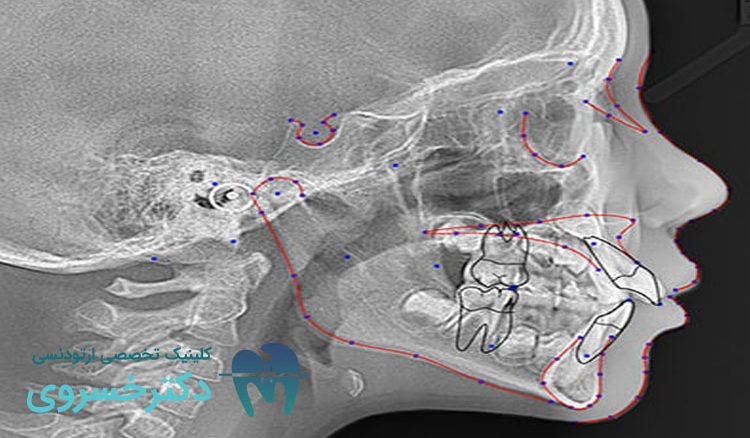

سفالومتری یکی از روشهای تصویربرداری رادیوگرافی است و به منظور تهیه تصاویر جانبی و جلویی از سر و صورت بیمار مورد استفاده قرار میگیرد. این تصاویر موقعیت دندانها، فکها و ساختارهای صورت نسبت به یکدیگر را ارزیابی میکنند. در این روش از یک اشعه ایکس استفاده شده که از طریق سر بیمار عبور کرده و تصویری دقیق و دو بعدی از استخوانها، دندانها و بافتهای نرم را ارائه میدهد.

ارتودنتیستها با استفاده از سفالومتری روابط دندانی و فکی را به دقت تحلیل میکنند و تمامی ناهنجاریهای دندانی و فکی را تشخیص میدهند. این تصاویر علاوه بر ارزیابی وضعیت فعلی دندانها میتوانند برای مشاهده تغییرات در طول درمان نیز مفید واقع شود.

امروزه با پیشرفت فناوری، تکنیکهای سفالومتری نیز بهبود یافتهاند و امکانات جدیدی را در اختیار متخصصین قرار میدهند. استفاده از نرمافزارهای تحلیل تصاویر سفالومتری به ارتودنتیستها امکان میدهد که تصاویر را بهصورت دقیقتر و با جزئیات بیشتری بررسی کنند.

تحلیل دیجیتالی سفالومتری

یکی از پیشرفتهای مهم در این زمینه، استفاده از نرمافزارهای تحلیل دیجیتالی سفالومتری است. این نرمافزارها میتوانند بهطور خودکار ابعاد و زوایای مختلف دندانها و فکها را محاسبه کنند و اطلاعات دقیقی را در اختیار ارتودنتیست قرار دهند. این تکنولوژی علاوه بر افزایش دقت، زمان تحلیل تصاویر را نیز بهطور قابل توجهی کاهش میدهد.